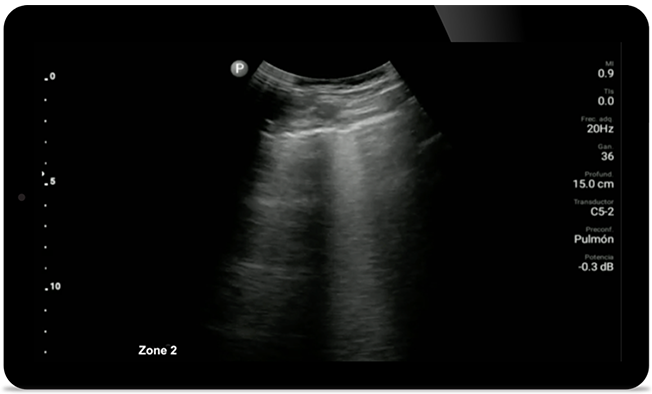

Lumify может помочь получить результаты, схожие с КТ грудной клетки, при оценке пневмонии и респираторного дистресс-синдрома взрослых.

• Расширенный диапазон рабочих частот — от 12 до 4 МГц. • Размер апертуры: 34 мм. • 2D, управляемый цветной доплеровский режим, M-режим, продвинутая визуализация XRES и многомерная гармоническая визуализация, SonoCT. • Визуализация с высоким разрешением для исследования неглубоких структур: мягких тканей, сосудов, поверхностных тканей, костно-мышечной системы и легких. • Маркер центральной линии. • Датчик USB-C со сменным кабелем.